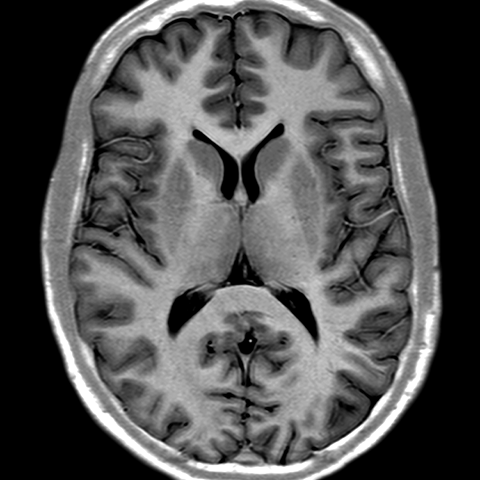

Cerebral Hemispheres, MR (normal) [2 of 9]